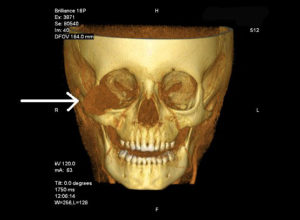

There are many different types and locations of orbital tumors that can occur. A thorough past medical history is taken with a particular note of any previous tumors. As with the treatment of any other orbital abnormality, it is imperative that all patients have a thorough examination of their eye. This starts with a measurement of the visual acuity. A complete examination of the ocular surface, tear film and contents of the eye is performed. Frequently, orbital tumors can occur in association with a systemic illness which must be addressed.

The Surgery